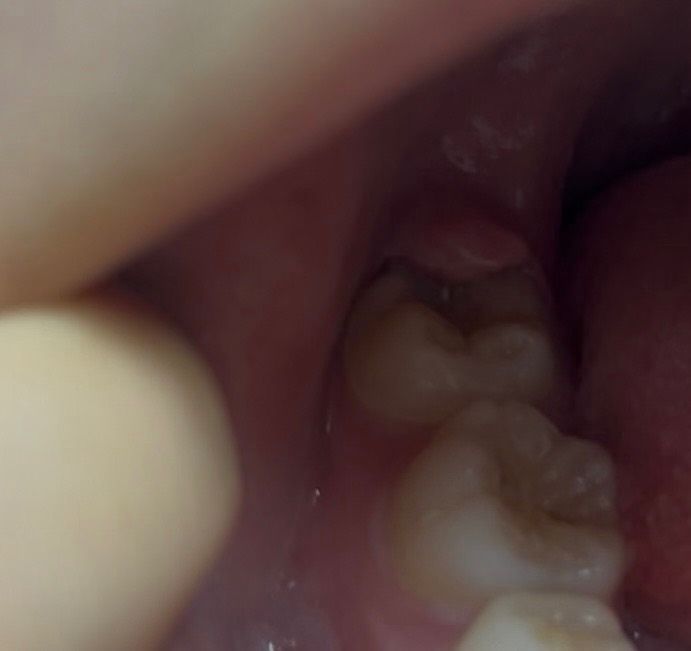

잇몸 거슬림 부음 약간의 통증 사랑니인가요?

며칠전부터 제일 안쪽 잇몸들 붓기 시작하더니

이제는 거슬리고 특히 왼쪽 잇몸 (첫번째사진) 은

통증도 느껴집니다 입에 힘주고 웃을때 엄청 거슬리고

이게 어금니가자라면서 잇몸이 붓고 통증이오는건지

아니면 사랑니의신호인지 ㅜ 궁금합니다

• 1번 째 사진

사진에 보이는건 사랑니는 아닌거 같고 가장 뒤 어금니 맹출이 다안됫거나 잇몸이 과증식된 상태 같습니다.

네 잇몸안에 파묻힌 사랑니가 치관주위염을 유발해 잇몸이 붓고, 아픈 것 같습니다 사랑니 발치 상담 받아보세요